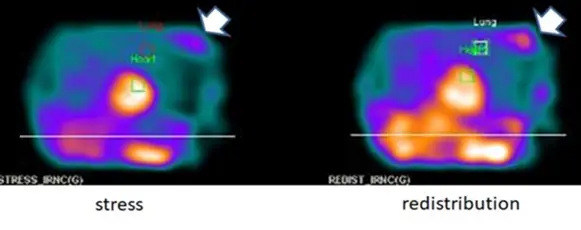

題目提供了兩張核醫平面(Planar)或投影(Projection)影像,左側標註為「stress」(壓力測試期),右側標註為「redistribution」(重分布期)。此種「壓力-重分布」的造影流程特徵,強烈提示使用的放射性同位素為 201Tl-TlCl(Thallium-201)。

- 肺部攝取(Lung Uptake):影像中央綠色框線標示為「Heart」,而其上方標示「Lung」的區域可見明顯的放射性同位素廣泛分佈。在壓力測試影像中,明顯的肺部活性滯留提示左室舒張末期壓力(LVEDP)異常上升。

- 心外異常攝取(Extracardiac uptake):影像右側(依放射學常規對應為病患的左胸壁)有一明顯的白色箭頭,指向一個局部異常的放射性高攝取區域(Focal uptake)。該位置對應左乳房的解剖位置,且在 stress 與 redistribution 影像皆持續存在。

- (D) 在心臟以外區域若有201Tl-TlCl蓄積,如圖箭頭所示,有可能是乳房腫瘤

- 正確。201Tl 作為鉀離子(K+)的類似物,除了能進入正常心肌細胞外,也會透過 Na+/K+ ATPase 幫浦進入高血流與高代謝的惡性腫瘤細胞內。臨床實務中,若在 MPI 影像視野內意外發現乳房、肺部或縱膈腔的局部高活性蓄積(Incidental uptake),須高度懷疑惡性腫瘤。配合影像分析,圖中箭頭所指的左側胸壁結節狀活性,的確有極大可能是乳房腫瘤。